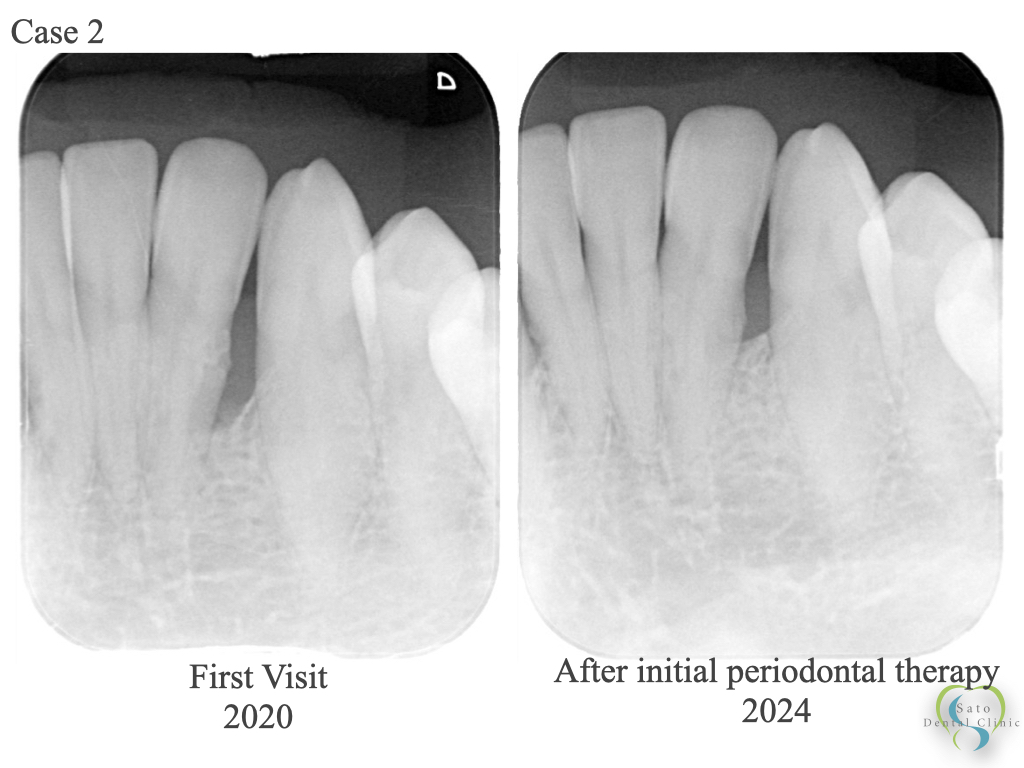

歯周治療プラクティスマニュアル = Periodontal therapy :… 図解。Periodontal Disease Treatment] When it comes to treating。歯のマメ知識-300x219.png。「歯周治療プラクティスマニュアル = Periodontal therapy : 基礎から臨床まで : 図解」五味 一博 / 五味 一博 / 長野 孝俊 / 長野 孝俊 / 白川 哲 / 八島 章博 / 松島 友二 / 鈴木 琢磨 / 梶山 創太郎定価: ¥ 10000#五味一博 #五味_一博 #五味一博 #五味_一博 #長野孝俊 #長野_孝俊 #長野孝俊 #長野_孝俊 #白川哲 #白川_哲 #八島章博 #八島_章博 #松島友二 #松島_友二 #鈴木琢磨 #鈴木_琢磨 #梶山創太郎 #梶山_創太郎 #本 #自然/医療・薬学・健康一度読んだだけです。Management of Periodontal Disease with Adjunctive Therapy。